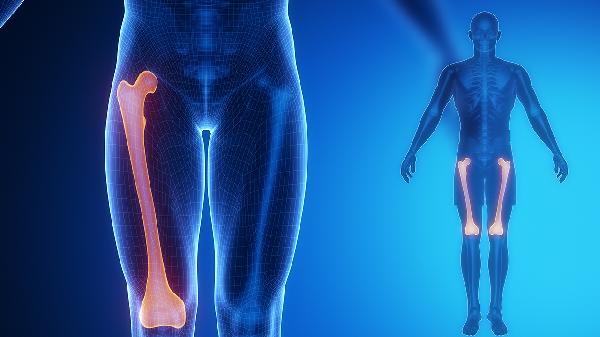

4、坐骨神经痛

坐骨神经痛可由腰椎间盘突出、梨状肌综合征等疾病引起,表现为臀部至下肢的放射性疼痛。筋骨痛消丸通过改善局部气血循环,有助于缓解坐骨神经痛的症状。患者使用时应避免久坐久站,必要时配合物理治疗。其他治疗药物还包括甲钴胺片、布洛芬缓释胶囊等。